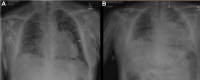

A 40-Year-Old Man With Tricuspid Atresia, Status Post-Fontan, With Severe COVID-19 Pneumonia and Pneumothorax

We report a case of COVID-19 in an adult single-ventricle patient post-Fontan-to our knowledge, the first report in this population documenting the use of the latest management recommendations for this novel disease. Additionally, this patient had significant pre-existing ventricular dysfunction, valvular disease, and comorbidities including HIV. (Level of Difficulty: Advanced.).